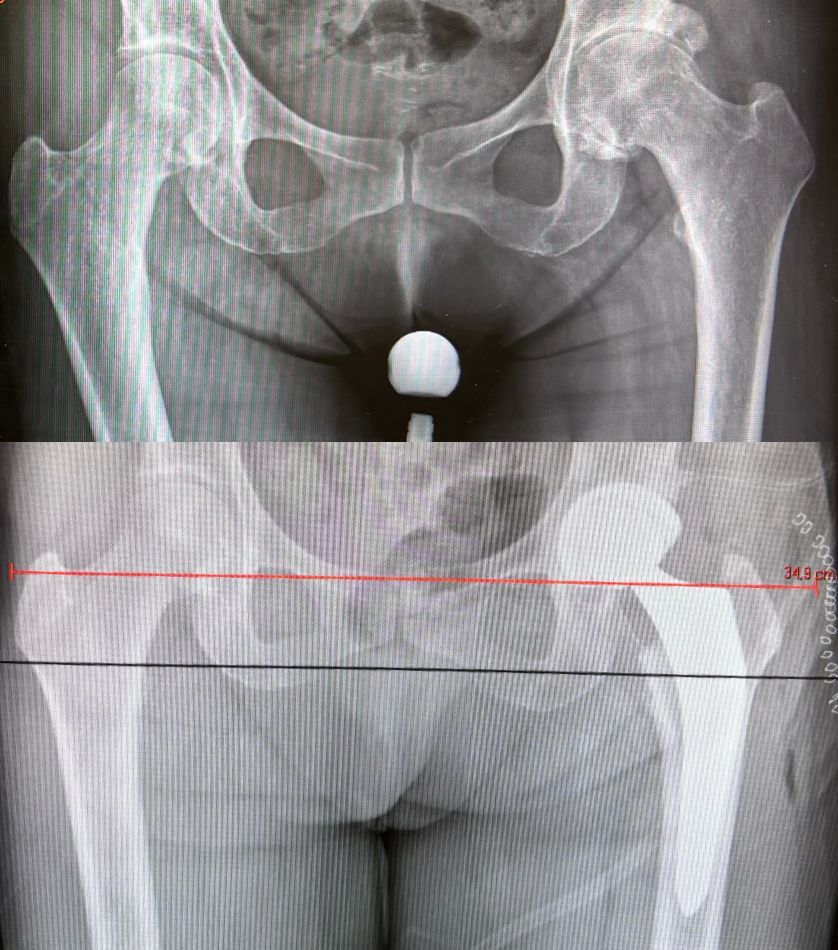

Ho maturato una solida esperienza nella chirurgia protesica mini-invasiva di anca e ginocchio. Eseguo interventi di protesi di anca mediante accesso anteriore “bikini” e accesso posterolaterale, interventi di protesi di ginocchio sia monocompartimentale che totale. Tratto la traumatologia sportiva di ginocchio e spalla mediante l’utilizzo di tecniche artroscopiche mini-invasive.